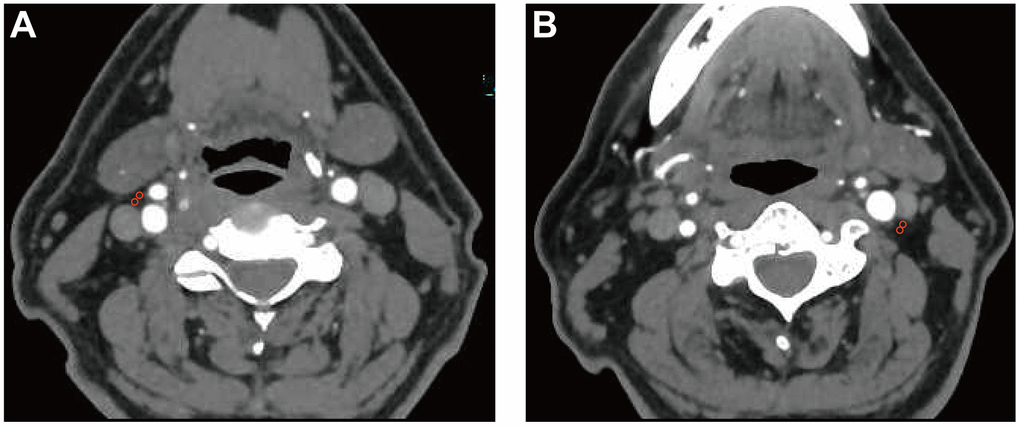

The density of the pericarotid fat surrounding the extracranial ICA can be measured via Hounsfield units (HU) on routine CTA imaging. We referred to an established approach previously described in [2] using predefined image display settings (window width, 500 HU; window center, 100 HU). We placed 2 regions of interest (ROIs) (3 mm2 in diameter) in the perivascular fat on both sides of the ICAs (Figure 3). The ROIs were placed at least 1 mm from the outer margin of the carotid artery wall to exclude the carotid artery wall and surrounding soft-tissue structures. The HU values were recorded from 3 discontinuous slices near the origin of the ICA, and then, the mean and maximum HU values were measured. In addition, if North American Symptomatic Carotid Endarterectomy Trial (NASCET)-defined ICA stenosis was present, we recorded the value at the maximum stenosis slices [33].

Figure 3. Pericarotid fat density analysis. Two regions of interest (3 mm2 in diameter) were placed in the pericarotid fat surrounding the origin of the internal carotid artery. (A) right internal carotid artery. (B) left internal carotid artery.